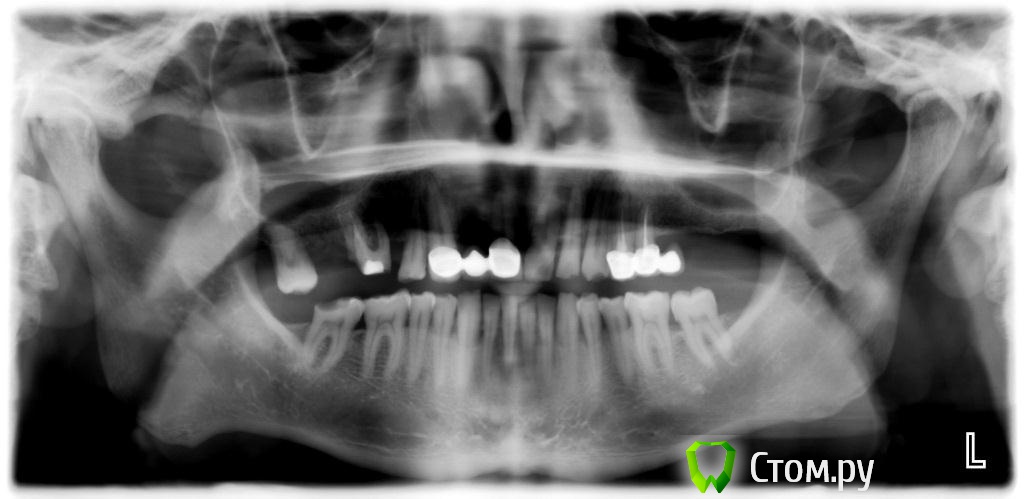

zzkz Опубликовано 1 марта, 2014 Поделиться Опубликовано 1 марта, 2014 (изменено) Первые дни после операци все шло отлично, сегодня при снятии швов обнаружил перфо на одном участке слизистой. Че то я очкую. Не полетит все ??Жалоб нет вообще никаких. Пациент чувствует себя замечтательно. За фото каюсь, пока еще только учусь, вечно не в фокус. Да и в синусах первые шаги(как-то не до фото было) фреза с корейского набора 400$ за набор. очень понравилосьAlfa-bio в обл. 27 зуба - 4.2*11.5; в обл. 26 - 3.65*11.5 + НКР Биоосс, мембрана Альфа Био а вот тут чуть в обморок не упал, мембрана что-ли оголилась. Видать фрезой там зацепил и не заметил, через неделю вылезла собака Ротовые ванночки с 0.05% ХГД и все. сказал ему что все идет по плану, но я то знаю что не так(Не сгниет там все? Изменено 1 марта, 2014 пользователем zzkz Ссылка на комментарий

vesvova Опубликовано 1 марта, 2014 Поделиться Опубликовано 1 марта, 2014 Судя по фото с имплантами ламина там врядли нужна была.Ширины в области шеек достаточно. Да и формирователи скорее всего поставить можно было. Ссылка на комментарий

zzkz Опубликовано 1 марта, 2014 Автор Поделиться Опубликовано 1 марта, 2014 Судя по фото с имплантами ламина там врядли нужна была.Ширины в области шеек достаточно. Да и формирователи скорее всего поставить можно было.это коллагеновая мембрана Альфа био(и правда похожа на ламину). Было НКР в области 26 зуба, тонкий гребень Ссылка на комментарий

Bazbi Опубликовано 16 марта, 2014 Поделиться Опубликовано 16 марта, 2014 Подскажите пожалуйста зачем здесь нужно было проводить нкр? Возле шейки импланта есть по 1-1.5 мм кости на глаз. Импланты spi? Ссылка на комментарий

SergeiVar Опубликовано 18 марта, 2014 Поделиться Опубликовано 18 марта, 2014 Набор для синус лифта DENTIUM , или Neobiote здесь Дентиум. Ссылка на комментарий